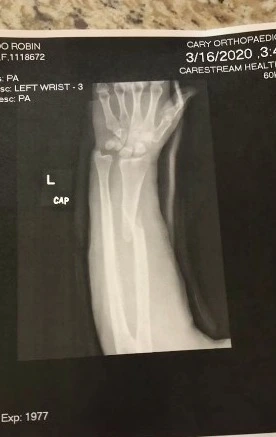

Machado further said, ‘The people standing around to help me took care of me and when my eyes fell on my arm, I saw that a bone was in a condition to penetrate my skin. I was immediately shocked and started crying in panic. I didn’t feel any pain at that time. After this I was taken to the hospital, where the doctors did my X-ray and told that my radius bone of my forearm was broken.